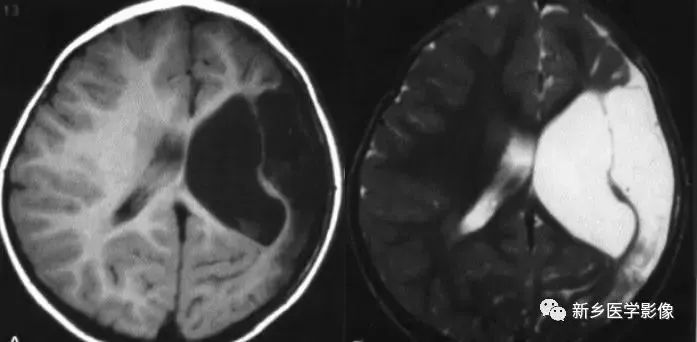

❷ 侧脑室神经上皮囊肿

通常位于侧脑室三角区,囊壁薄,通常显示不清。由于囊内含脑脊液,所以CT及MR都表现为脑脊液信号。